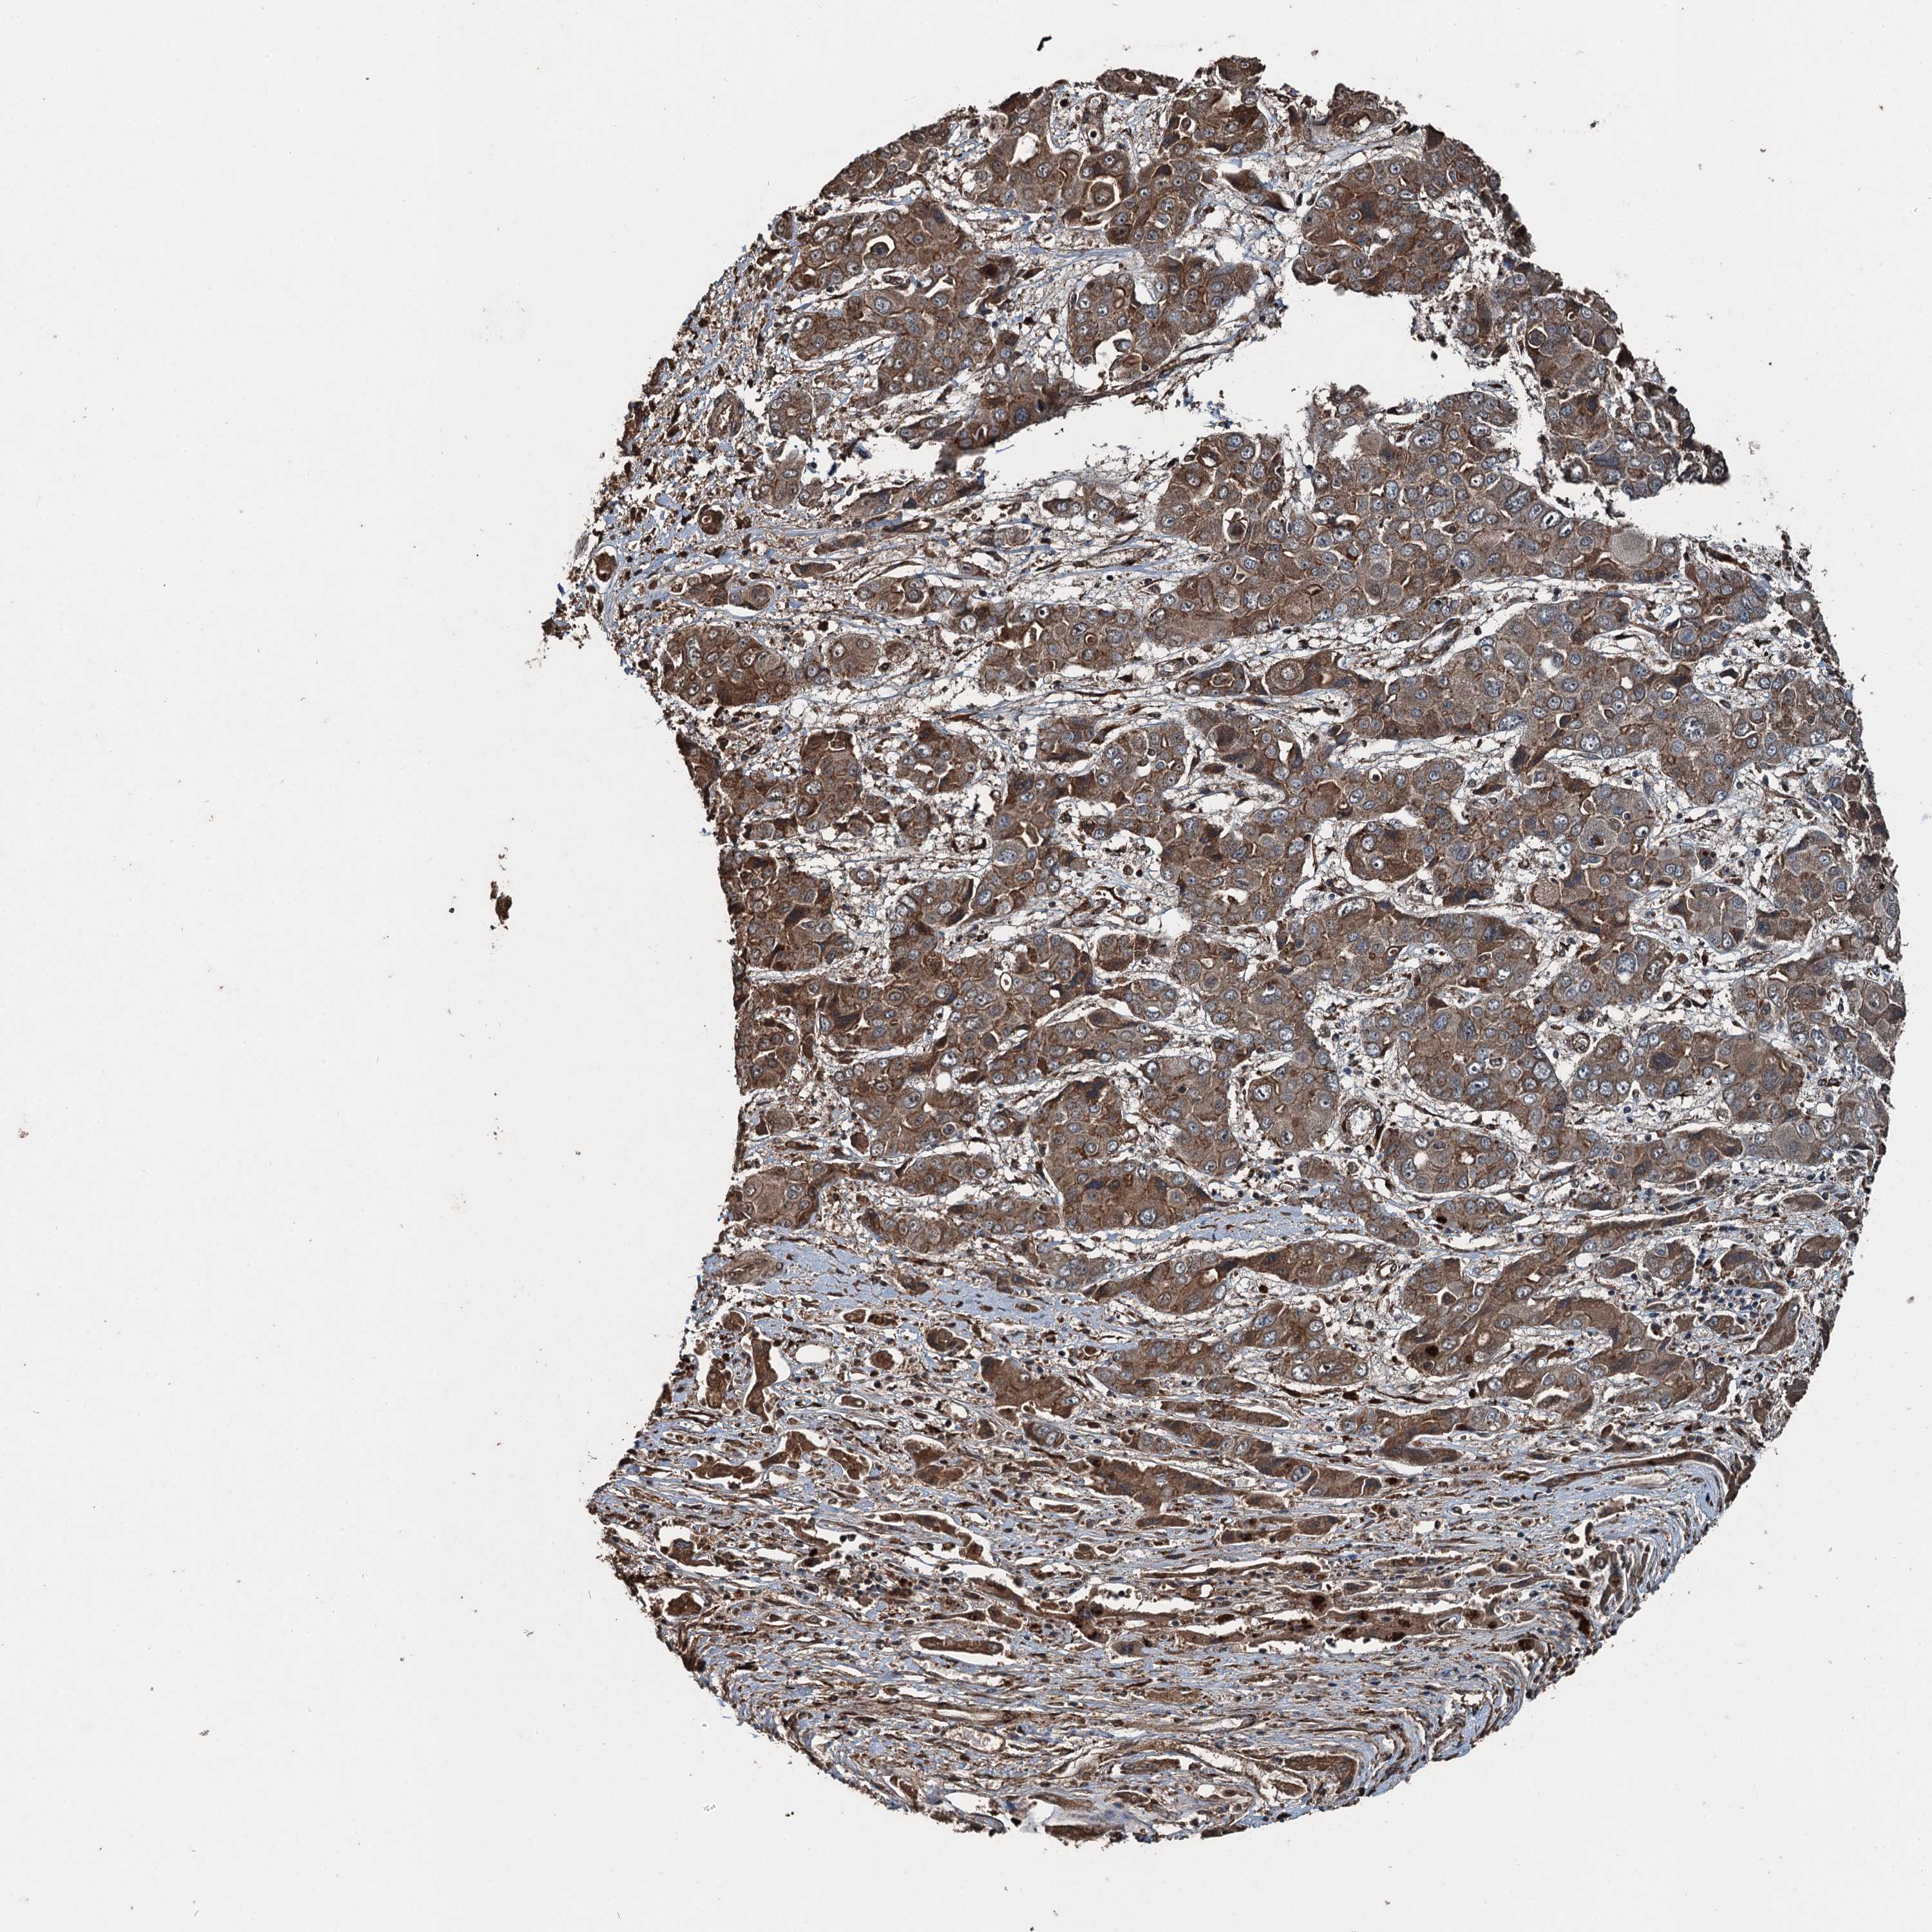

LIVER CANCER - Protein expressioni

A mouse-over function shows sample information and annotation data. Click on an image to view it in a full screen mode. Samples can be filtered based on level of antibody staining by selecting one or several of the following categories: high, medium, low and not detected. The assay and annotation is described here.

Note that samples used for immunohistochemistry by the Human Protein Atlas do not correspond to samples in the TCGA dataset.

Antibody stainingi

Antibody staining in the annotated cell types in the current human tissue is reported as not detected, low, medium, or high, based on conventional immunohistochemistry profiling in selected tissues. This score is based on the combination of the staining intensity and fraction of stained cells.

Each image is clickable and will lead to virtual microscopy that enables deeper exploration of all samples and also displays staining intensity scores, fraction scores and subcellular localization as well as patient and tissue information for each sample.

Antibody HPA039687

Antibody HPA040036

Staining

High

Medium

Low

Not detected

Intensity

Strong

Moderate

Weak

Negative

Quantity

>75%

75%-25%

<25%

None

Location

Nuclear

Cytoplasmic/membranous

Cytoplasmic/membranous,nuclear

Cholangiocarcinoma

Carcinoma, Hepatocellular, NOS